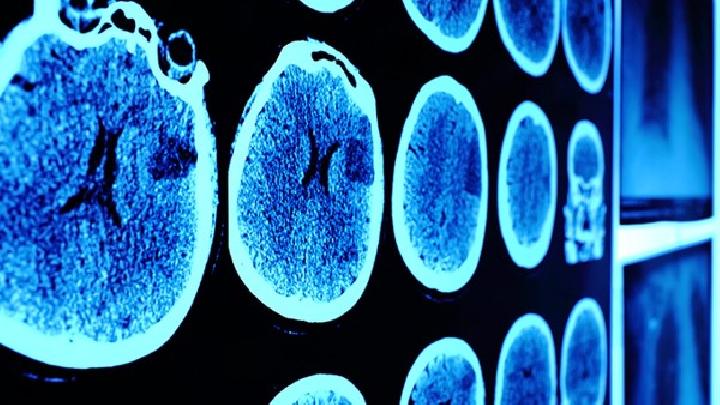

脑水肿的检查和诊断,CT或MRI直接提示脑水肿最可靠的诊断方法,CT在病变周围或白质区域,不同范围的低密度区域,MRI在T1或T2与加权像相比,水肿区是高信号CT扫描结果更准确。